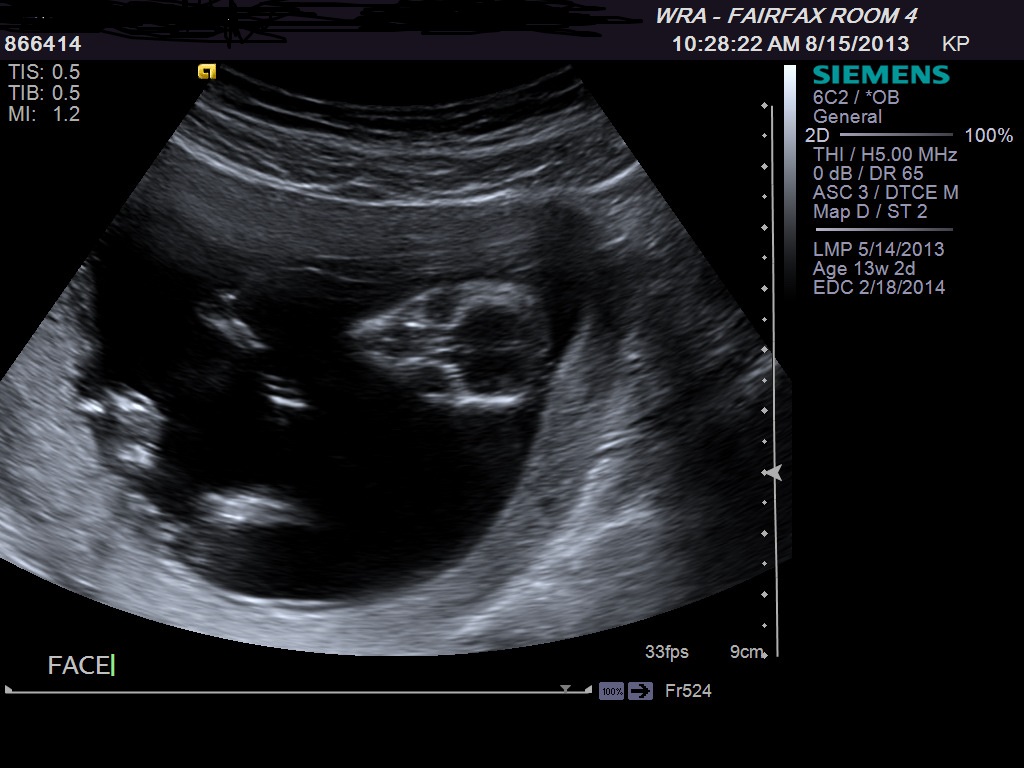

How far along are you? Thinking maybe girl...